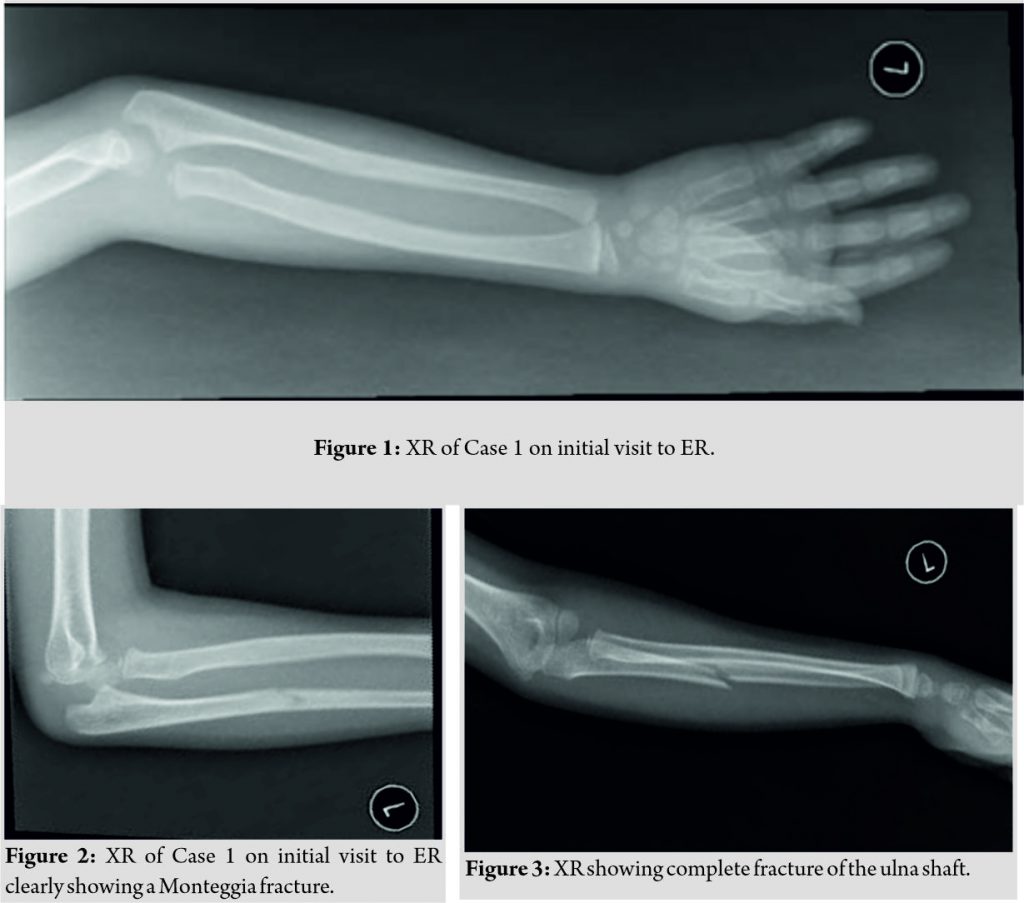

A 5-year-old medically free female presented to us after falling down 10 days ago. She went to the Emergency Room immediately following her fall complaining of the left arm pain, she was discharged on a splint and paracetamol with the diagnosis of a greenstick fracture of her left ulna by the ER physician (Fig. 1, 2). The pain has shown little improvement and she refused to move her arm completely. She had no other complaints on systemic review.

On reviewing her X-rays at the time of diagnosis, the lateral elbow X-ray has clearly shown a radial head dislocation with a proximal ulna fracture, the anteroposterior (AP) X-ray was poor quality and did not show any fracture (Fig. 2), on repeating the forearm X-ray, a complete fracture of the ulna shaft was noted (Fig. 3).

The patient was admitted for further treatment and consented for closed reduction under general anesthesia with the possibility of internal fixation versus open reduction and internal fixation. Intraoperatively, the patient was placed supine with the left arm on the arm board and was draped with strict aseptic technique due to the possibility of converting to open reduction. The traction-countertraction method was used to obtain reduction and slight pressure on the radial head to reduce it in place. The radial head was reduced and after a trial of range of motion and intraoperative fluoroscopy it was found to be stable, the patient was placed in an above elbow cast in slight hyperflexion to maintain reduction (Fig. 4, 5).